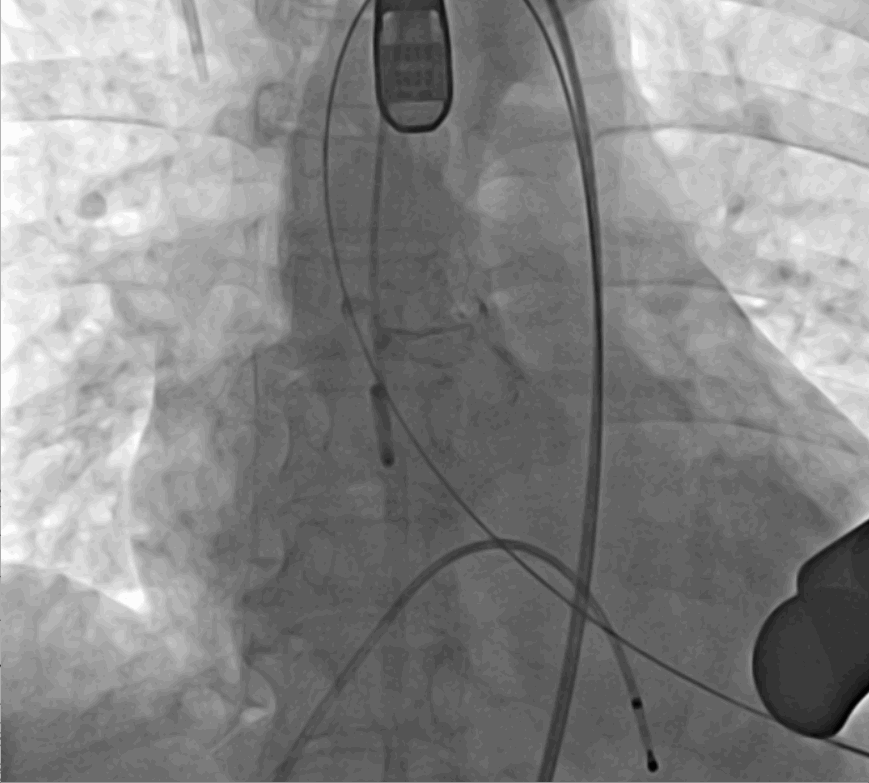

術(shù)中釋放定位鍵后DSA影像圖

手術(shù)采用經(jīng)心尖入路,對患者進(jìn)行全麻后,在左側(cè)心尖處做3-4cm微創(chuàng)手術(shù)切口,在DSA及超聲引導(dǎo)下手術(shù)順利完成。從導(dǎo)入器械到完成瓣膜置入,僅耗時約10分鐘。術(shù)后即刻主動脈瓣返流程度由術(shù)前大量返流轉(zhuǎn)為消失,患者于導(dǎo)管室拔除氣管插管,次日由ICU轉(zhuǎn)入普通病房。